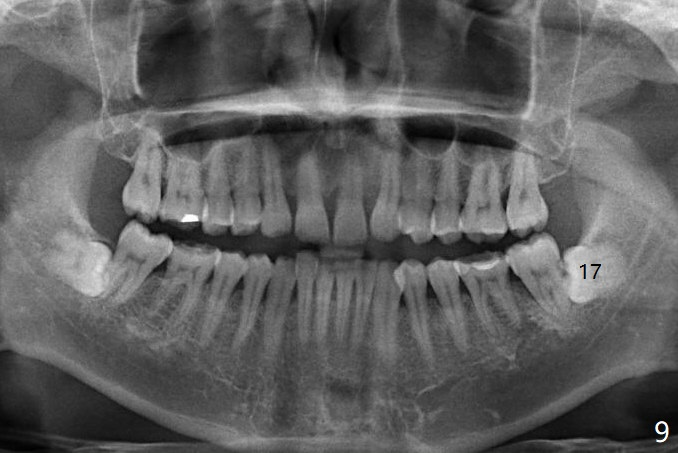

A 40-year-old man removes food debris from the lower left area, probably between #17 and 18, using Water Pik. Initially it looks as if the bone loss lingual (Fig.1 (CBCT with 3 sections) L) to #18 is derived from #17 (red curved arrow). Closer look shows generalized thickened periodontal ligament space at #18 (Fig.2 arrowheads). The patient requests extraction of the tooth #17; the tooth #18 seems non-salvageable. When an immediate implant is placed in the middle of the socket (Fig.3,4 (coronal section)), there is limited amount of the native bone to stabilize the implant (~1 mm). In contrast, there is approximately 5 mm of the native bone for primary stability if the implant is placed in the mesial slope of the fused socket (Fig.5 yellow dashed line). The implant should be placed buccally (B) to reduce the chance of nerve injury (Fig.4,6).

Photos are taken to show occlusal wear (bruxism) of the teeth #31 and 17 (Fig.7,8) prior to #17 extraction. Osteogen plug is placed in #17 socket after extraction and SRP at #18. The bone height at #18 distal seems to increase 2 years 4 months post extraction (Fig.9-12). The 1st molars have enamel hypoplasia with occlusal wear. In addition, occlusion is abnormal. There is no centric occlusion, partially contributing to periodontitis at #15 and 18. Crown is planned at #19 because of loss of occlusal amalgam (Fig.11 A, 12). Orthodontics may be required, although 2 insurances do not have orthodontic coverage for adults.